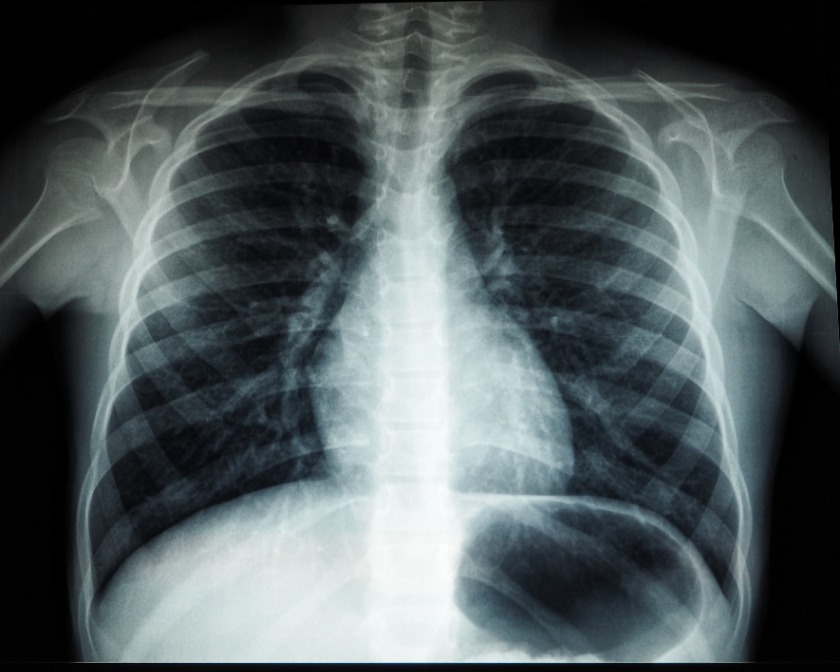

肋骨骨折が疑われる場合は、レントゲン撮影やCT撮影が行われます。また、内部の臓器の損傷が疑われる場合には、超音波検査や心電図、血液検査を行うこともあります。

肋骨骨折している患者のレントゲン写真

umanoide Unsplash

肋骨骨折の治療を行っても、後遺症が残ってしまうことがあります。骨折箇所が元のように癒着しない場合や、骨が欠損することで起こるのが変形障害で、後遺障害等級12級5号に該当します

後遺症の判断基準は、裸になったときに、目で見てわかる変形があるかどうかです。たとえレントゲンで変形が判っても、目で見てわからなければ認定されません。自賠責基準の場合、請求できる慰謝料の相場は94万円です。